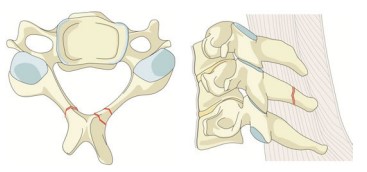

As fraturas tipo A2 (Split) são lesões raras e se caracterizam pelo traço coronal ou sagital envolvendo ambas as placas terminais, porém poupando o muro posterior da vértebra. Na fratura do tipo pinça (“pincer-type” A2.3), há deslocamento acentuado do fragmento ósseo anterior e pequenas zonas de descontinuidade, levando à redução da resistência à compressão e aumento da suscetibilidade do segmento afetado para ocorrência de pseudoartrose.